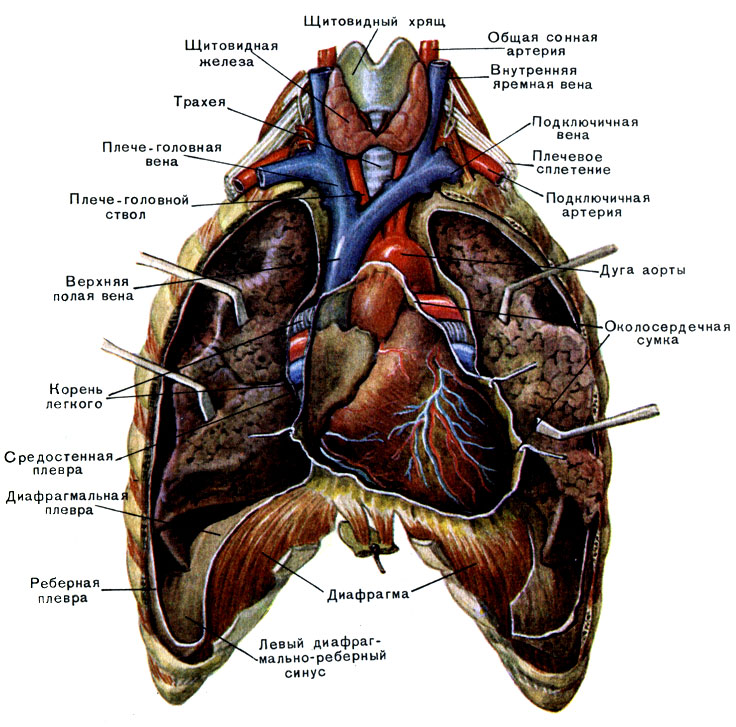

Анатомия Сердца: Расположение и Функции